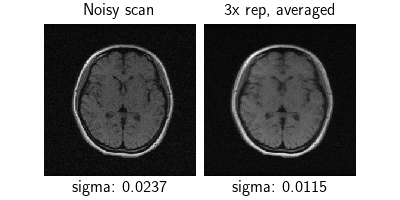

We load a single low-field T1 MRI scan (Oper 0.3T) from the M4Raw dataset [3], which contains multiple repetitions of the same scan with inter-scan motion. We use the first repetition as our noisy measurement, and average all three repetitions to create a βreferenceβ (which is still blurry due to motion).

Since the data is raw, we estimate the noise level in both the single scan and the averaged scan using patch covariance. Note that the averaged scan has lower noise as expected, but observe the motion blurring!

dinv.utils.plot(

{"Noisy scan": y, "3x rep, averaged": x},

subtitles=[

f"sigma: {noise_estimator(y).item():.4f}",

f"sigma: {noise_estimator(x).item():.4f}",

],

)